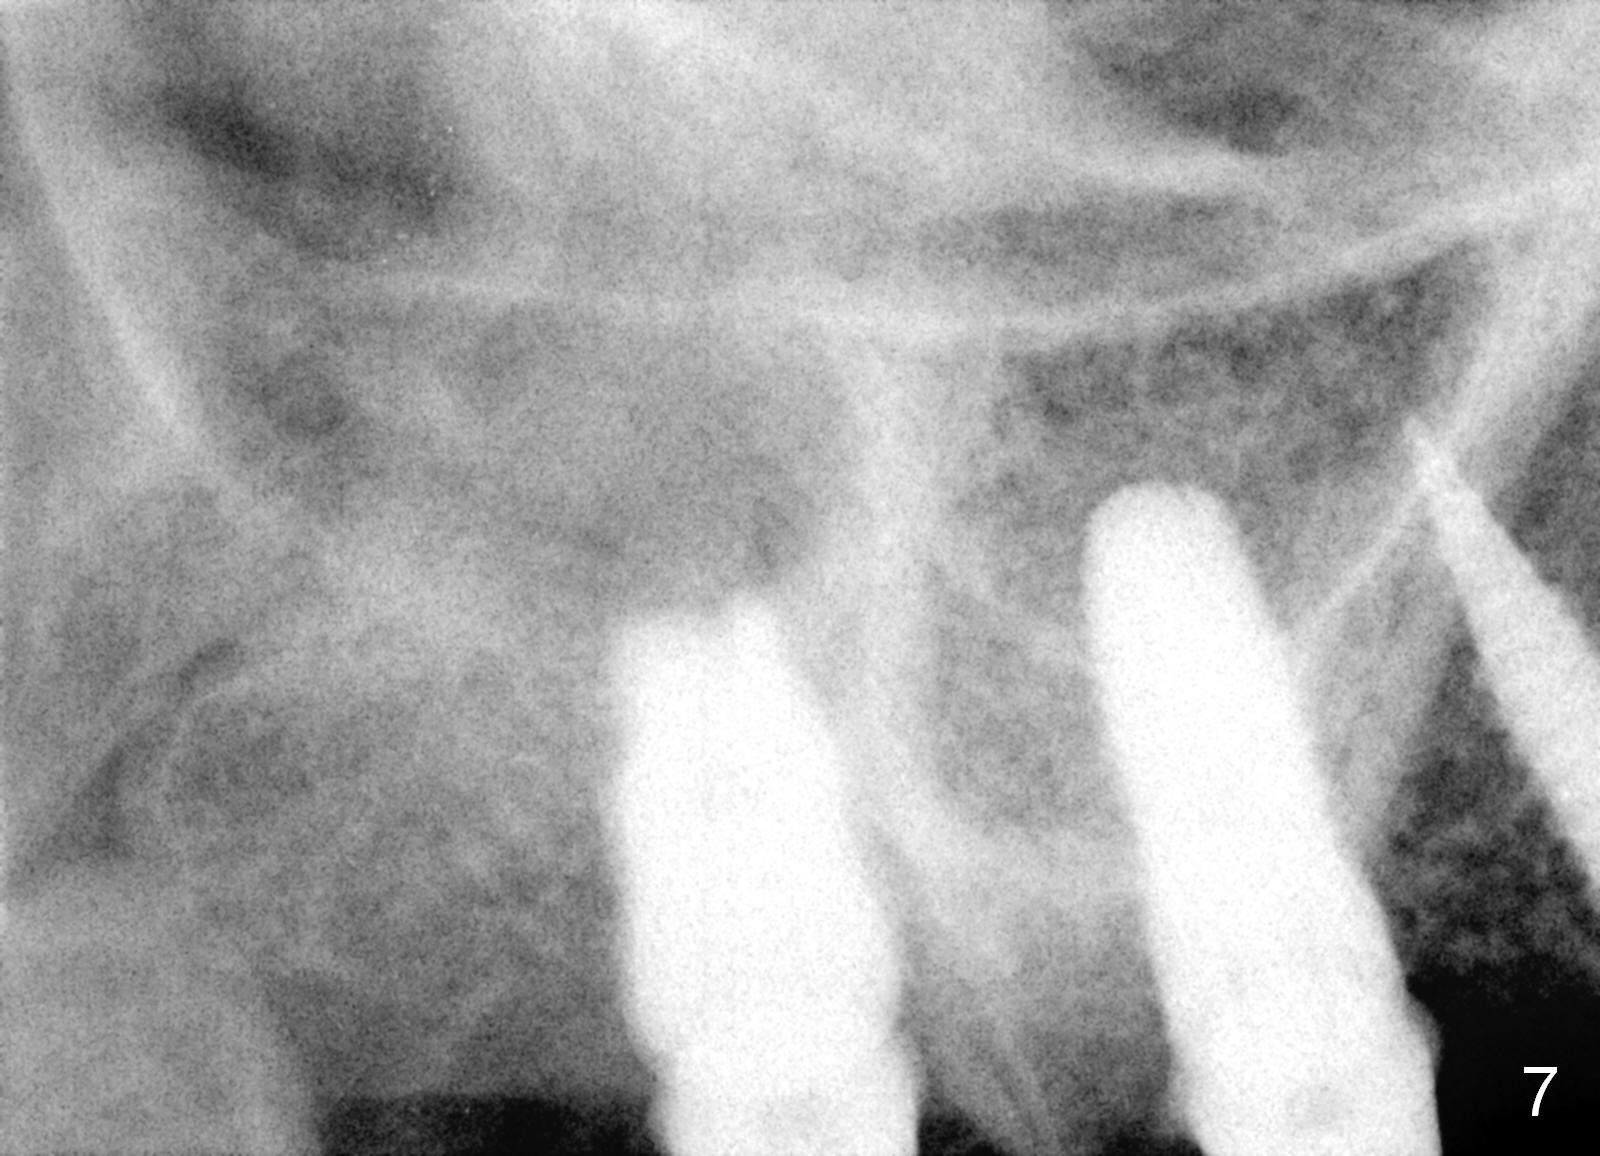

Osteotomy in the upper posteriors starts through a surgical stent for 12 mm. After incision, each osteotomy is examined, adjusted and extended 2 mm shy of intended (Fig.1,2). It appears that the trajectories at #4,5 are off (Fig.2). After re-adjustment, the trajectories are acceptable (Fig.3 (red dashed line; part of the root of the tooth #6)). Four implants are placed basically in accordance with the plan: 5.9x10 mm at #2, 5x14 at 3, and 3x14 mm 1-piece at 4 and 5 (Fig.4,5). Fig.6 shows the narrow ridge at #4 and 5 after implant placement. Although abutments are placed at #2 and 3, an immediate provisional bridge cannot be fabricated because of lack of enough clearance (supraeruption of the opposing dentition).

Provisional bridge is fabricated after wound healing. Four months postop, there is minimal bone resorption at the site of #5 (Fig.7,8). Single-unit crowns are fabricated.